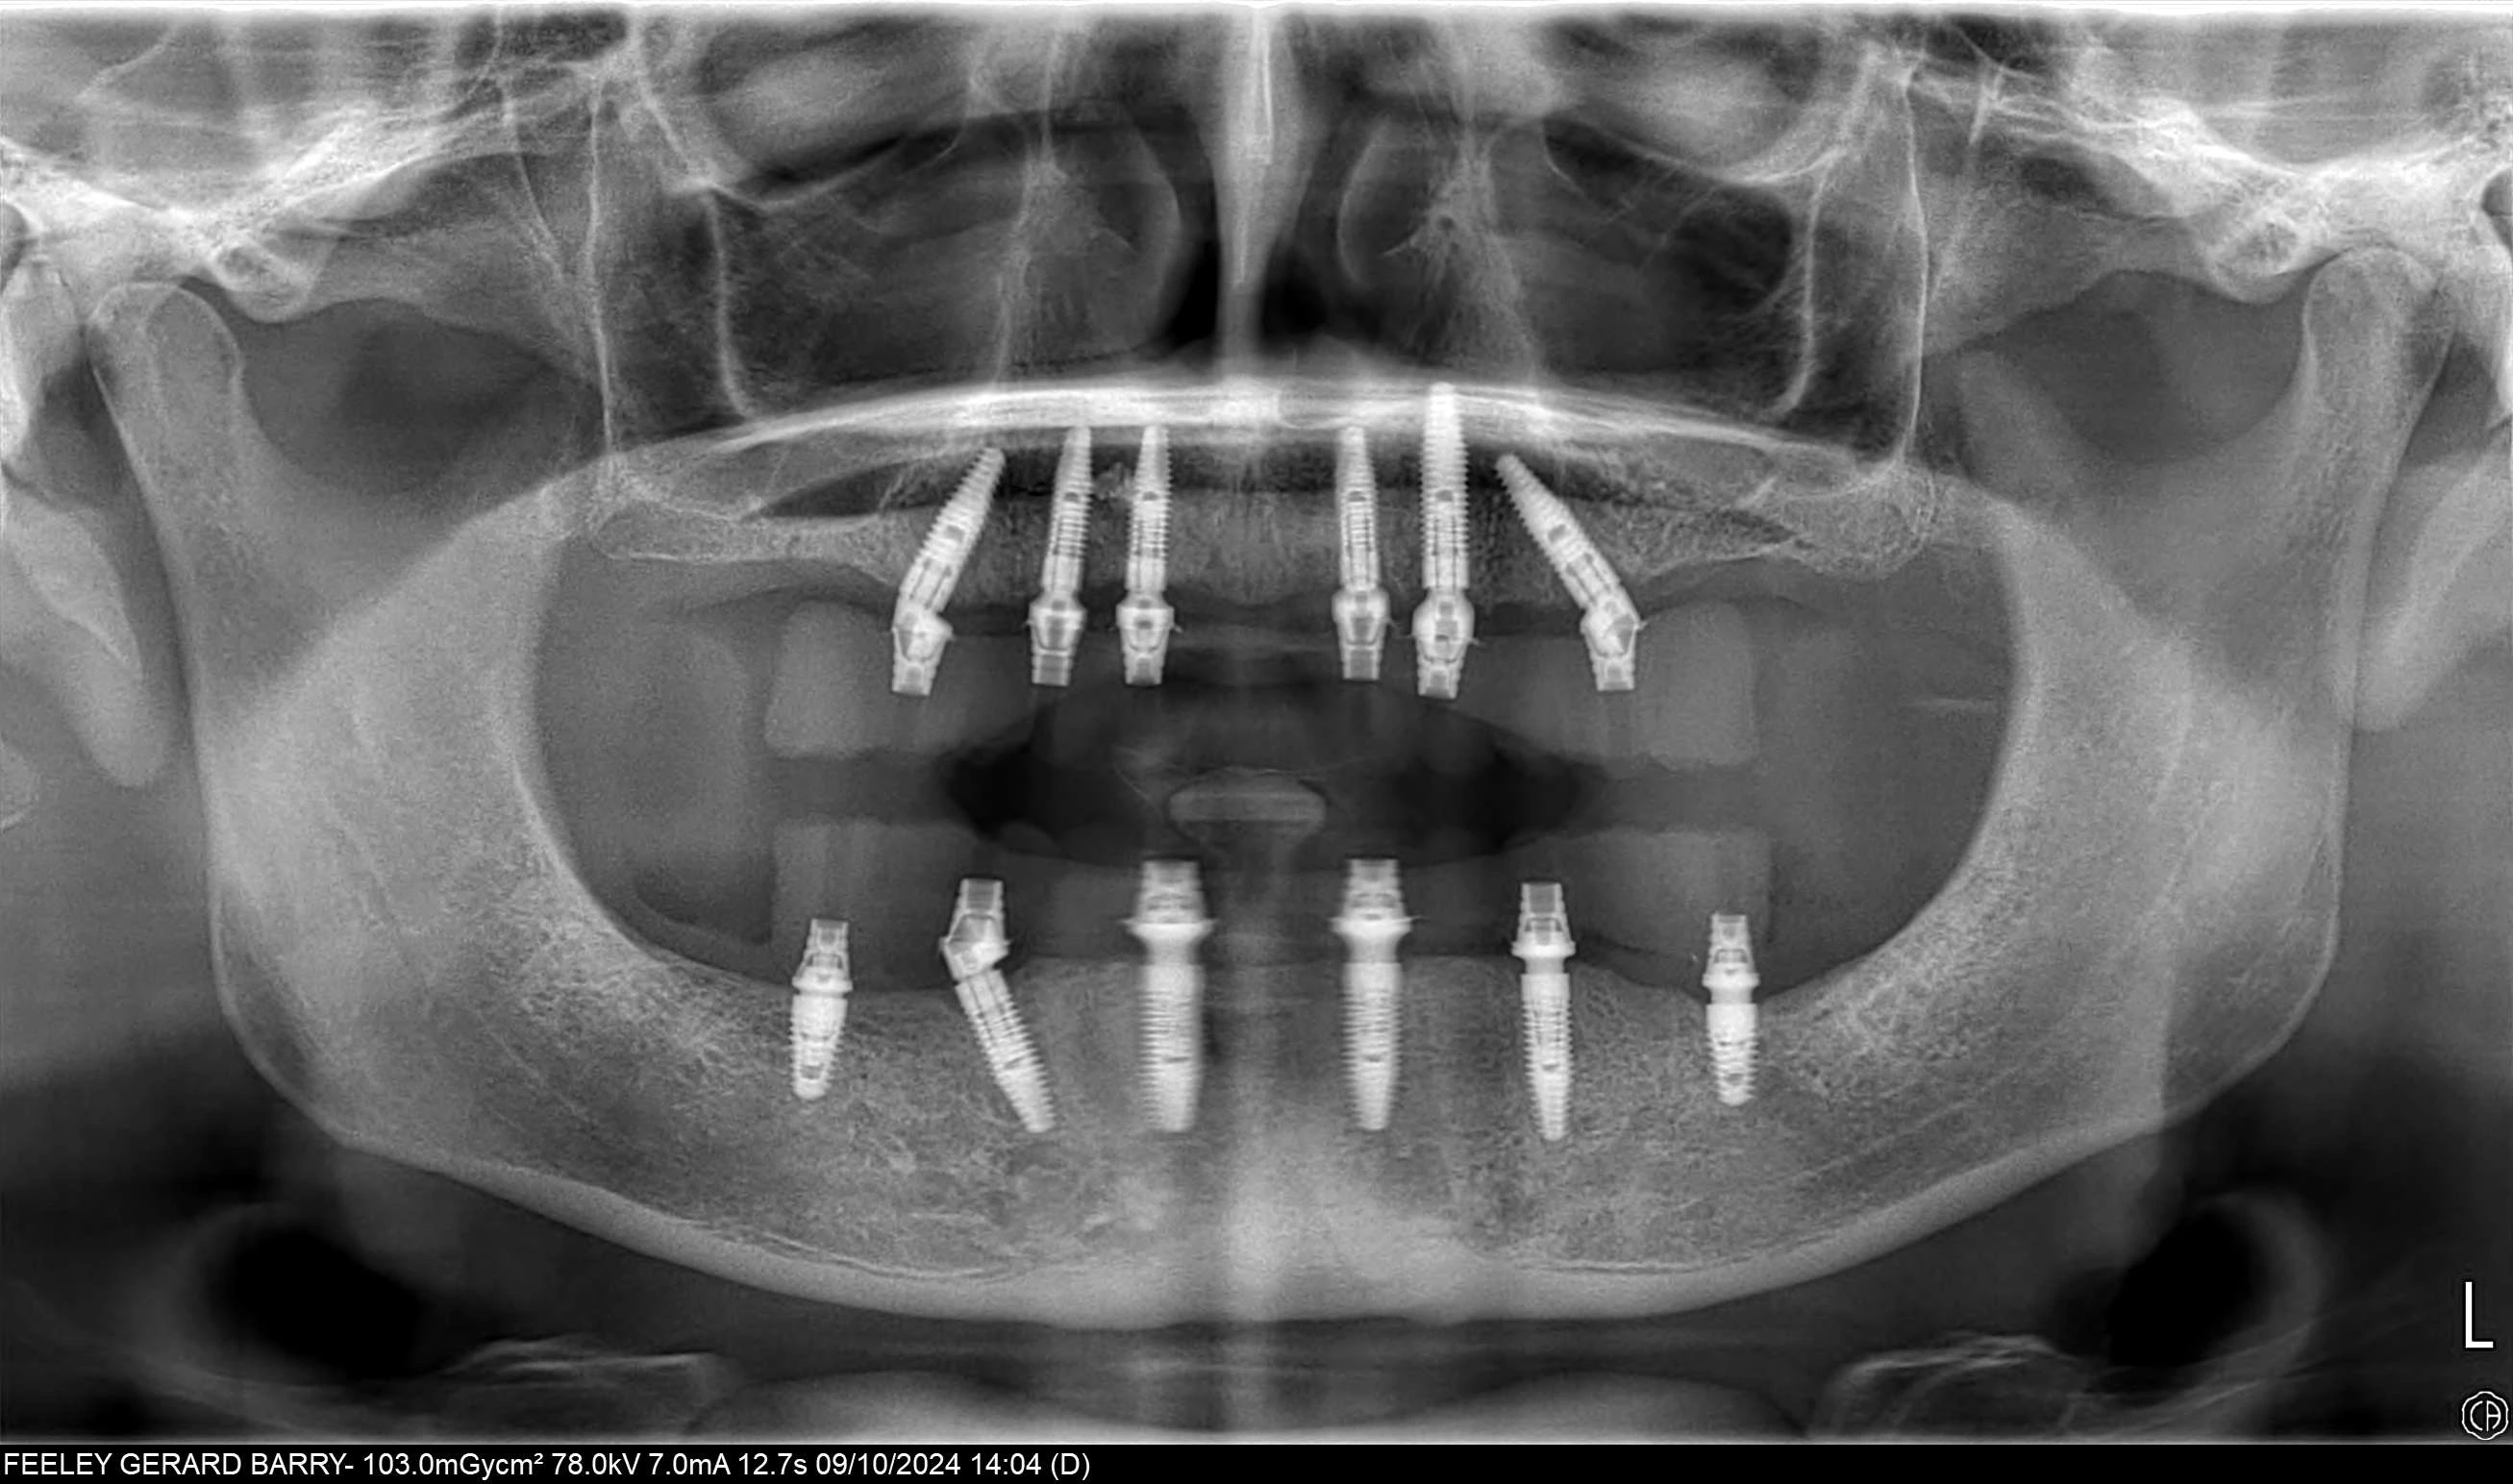

At Attelia, our All-on-6 restorations are supported by a titanium frame that provides superior durability and ensures chewing forces are distributed equally across all six implants. This enhances patient comfort and guarantees long-term success. To increase precision and functionality, we use multi-unit abutments on each implant, ensuring optimum angles, alignment, and a more natural bite.

This advanced approach—which requires high-level expertise, meticulous planning, and extensive clinical experience—not only improves overall stability and comfort but also provides a significant advantage for patients with mild to moderate bone loss. It allows for correct prosthetic positioning even when implants are placed at different angles.

While All-on-6 dental implant treatment often yields fast and effective results in patients with sufficient bone volume, we achieve high success rates even in cases with insufficient bone density through our solution-oriented approaches. Utilizing bone grafting (bone powder) and advanced surgical techniques, we adapt our treatment planning to the patient's anatomical limits, bringing the comfort of All-on-6 to even the most challenging cases.

Regardless of bone quantity, this approach ensures every patient is treated with a long-lasting roadmap best suited to their biological structure. This optimization stage creates an unshakable foundation for the titanium frame and aesthetic restorations built upon it. Furthermore, thanks to Zygomatic, Pterygoid, and Nasal implants, we possess the clinical equipment and expertise to perform complex treatments for challenging cases in a very short timeframe.